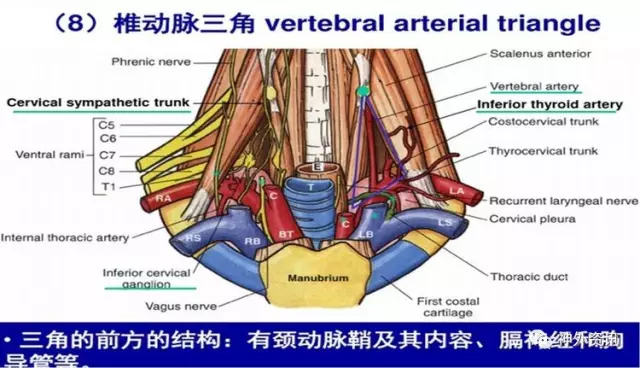

这个是左侧椎动脉三角的解剖:由于左椎开口位置深在,前方有胸导管横过,毗邻神经血管丰富,手术操作较右椎A开口段手术要困难一些,病人胸导管损伤、膈神经牵拉副损伤、胸膜顶损伤致气胸的风险较高,因而手术要求熟悉局部解剖,有较好的显微操作基础